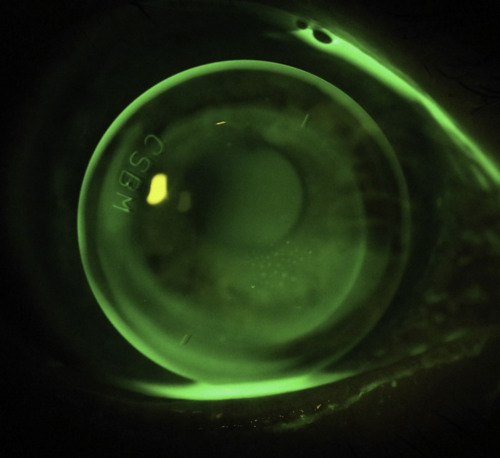

- Corneal topography will often struggle to measure the host tissue curvature due to the abrupt curvature change seen at the graft/host junction. This comes about from the ‘table-top’ configuration that many grafts have. Using composite maps on the Medmont software can assist here to get a better picture of the overall cornea (Fig 3). Anterior OCT can also help match peripheral curves to the host tissue curvature, as often excessive fluorescein or lifting-off during on-eye evaluation will not tell you much about what modifications to peripheral curves are required (Fig 4).

Fig 3. The advantage of composite topography maps with the E300 topographer. The composite map (right) shows a wider area that just the graft curvature seen on the single map (left)

Using lens design software, I was able to design a toric back optic zone radius (BOZR) that closely matched the corneal shape with reverse geometry peripheral curves steeper than the BOZR, that allowed the lens to lock into place and make the lens more stable (Fig 7). At the patient’s most recent appointment she was ecstatic with the results. The lenses were no longer flicking out, were far more comfortable on the eye and achieved excellent 6/6 vision in each eye. She could now drive comfortably at night which she was reluctant to do with her previous lenses! Her left lens had a BOZR difference of 3.6mm between the two meridians which highlights how extreme some of these designs have to be to fit an irregular corneal graft.

Fig 7. My patient’s new right lens. As one of my colleagues eloquently puts it, inevitably RGPs on grafts still end up looking like a ‘dog’s breakfast’, however this lens has a much better central alignment and better peripheral fit than the original due to the toric reverse geometry design